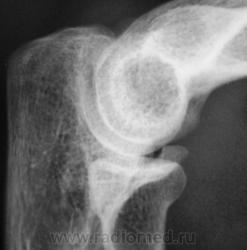

Травма. Пациент направлен на рентгенографию локтевого сустава.

Травма.    Пациент направлен на рентгенографию локтевого сустава. Исследование произведено.